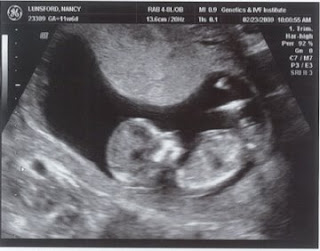

This morning, Michael and I got a close up look at our little baby when we had our 12 week ultrasound -- our last of the first trimester, which ends next week. Although we were told we'd have to wait until week 18 or 20, we discovered that the office had failed to schedule me for a routine prenatal test that would give us the opportunity to get a glimpse sooner. Naturally, we scheduled it right away. It was a wonderful experience. In spite of all the books I've read I wasn't quite expecting to see our baby looking as "baby-like" as he or she did. All along I have pictured our baby much in the way he or she appeared in our last ultrasound... How Baby Luns has grown!

The baby seemed very peaceful and didn't move at all so it made it much easier for us to get a good look. We had the chance to get a close-up of his or her little face, nose, legs, arms and feet. Its hand was up at its face as though it was sucking its thumb. (I really hate to use the word "it" but when I wrote "his or her" it made the sentence nearly unreadable.) I can't wait to find out what we should call our baby... but for now seeing his or her face was the perfect medicine for all that's been ailing me. I recently decided to stop taking all my medicines and I am just trying to pray through the morning sickness, which was not helped by nearly 24 hours of being in the car this past weekend travelling between Virginia and Tennesee. I'm hopeful that I'll be like "most women" who see an end to the nausea at the end of the first trimester. Right now, I feel invincible! I just keep picturing that precious face. It makes it all much more bearable. Couldn't wait to share these pictures with all of you!